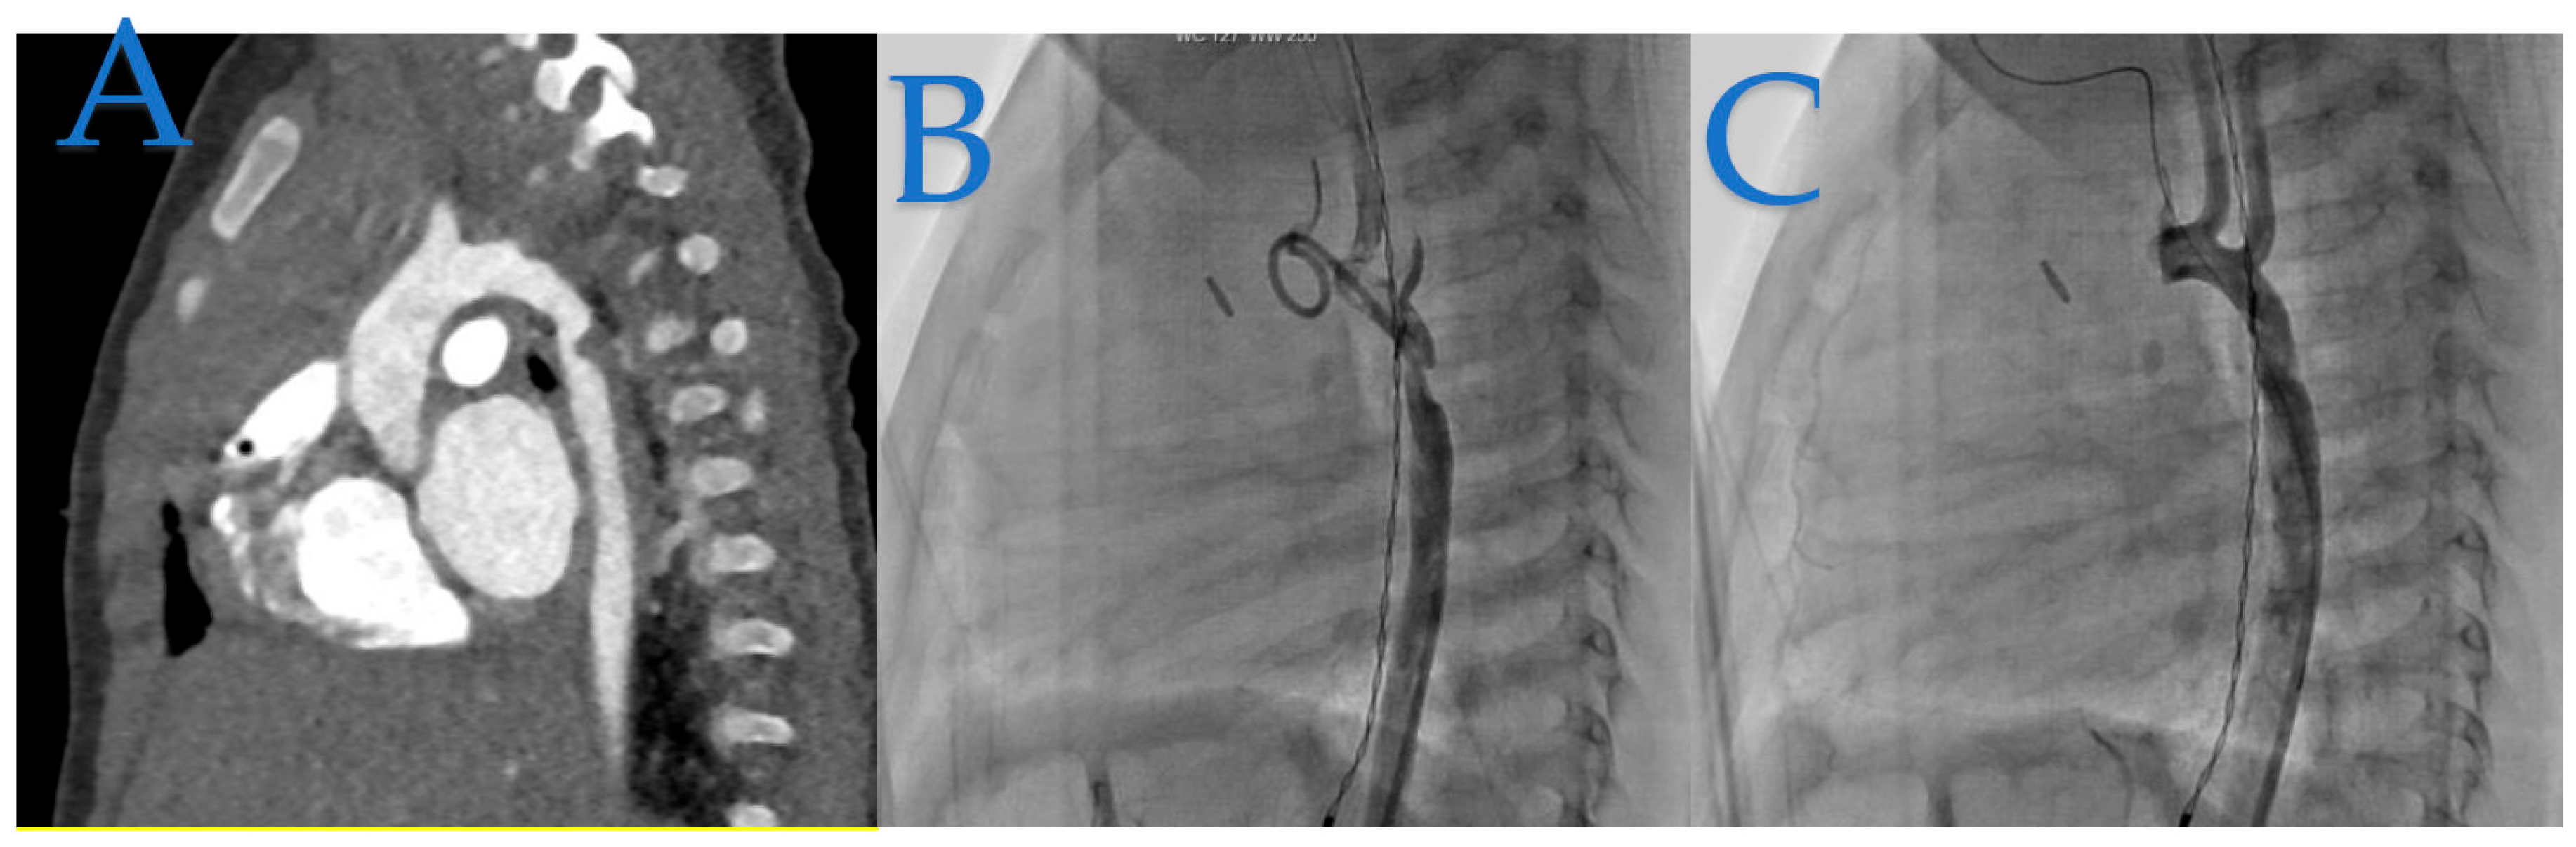

In Figure 3, we illustrate the case of a 23-year-old woman who was incidentally diagnosed with native coarctation during a routine check-up for hypertension during her pregnancy.

Figure 3. Adult-Onset Coarctation Diagnosis and Treatment. (A): The angioscanner reveals a 4 mm isthmic coarctation in this adult patient. (B): Confirmation through profile aortic angiography demonstrates a transcoarctation gradient of 34 mmHg. (C): The patient was successfully treated with a 43 mm XXL Andrastent bare stent mounted on a 14x40 mm BiB Balloon, yielding ideal results. (D): The stent was initially placed and later redilated with a larger balloon to optimize its positioning in the aorta. The angiography clearly shows the bare stent properly as opposed to the aortic wall, with no evidence of aortic wall damage.